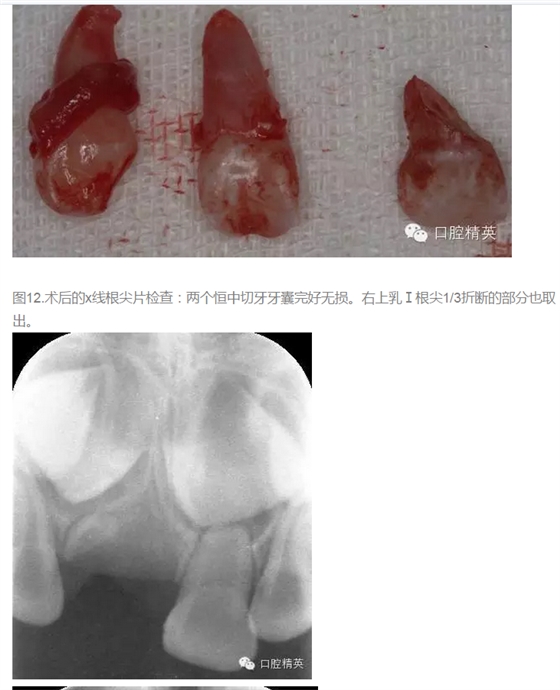

患者、王xx、4歲、男孩。主訴:上前牙松動,要求治療?,F(xiàn)病史:一個月前、患兒不慎碰墻,導(dǎo)致上前牙受傷,當(dāng)時未做任何處理,最近兩天,患兒感覺上前牙松動,輕微疼痛,遂來我院兒牙科就診。??茩z查:右上乳Ⅰ松動一度。右上乳Ⅰ近中側(cè)有一畸形牙尖。x線根尖片:右上乳Ⅰ根尖1/3折斷,其近中有一多生牙,該多生牙壓迫右上乳Ⅰ近中根面吸收。同時發(fā)現(xiàn)左上乳Ⅰ也有一顆多生牙。診斷:(1)右上乳Ⅰ根折。(2)多生牙。處理:1)建議拔除右上乳Ⅰ和其下方多生牙,待患兒到能配合的年紀(jì)再拔除左側(cè)乳Ⅰ下方的多生牙。2)同時拔除右上乳Ⅰ和兩枚多生牙。給患兒目前講明兩種方案的利弊,患者選擇第二套方案。